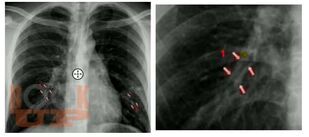

В учебном пособии изложены современные представления о наиболее значимых заболеваниях легких: об остром и хроническом бронхите, хронической обструктивной болезни легких, бронхиальной астме, пневмониях, бронхоэктатической болезни. Представлена современная информация об этиологии, патогенезе, особенностях клинической картины выше указанных заболеваний. В пособии изложены современные принципы терапии данных заболеваний, даны стандарты по применению антибактериальных препаратов при пневмониях. В пособие включены тестовые задания и ситуационные задачи. Учебное пособие содержит 27 таблиц и 18 рисунков.